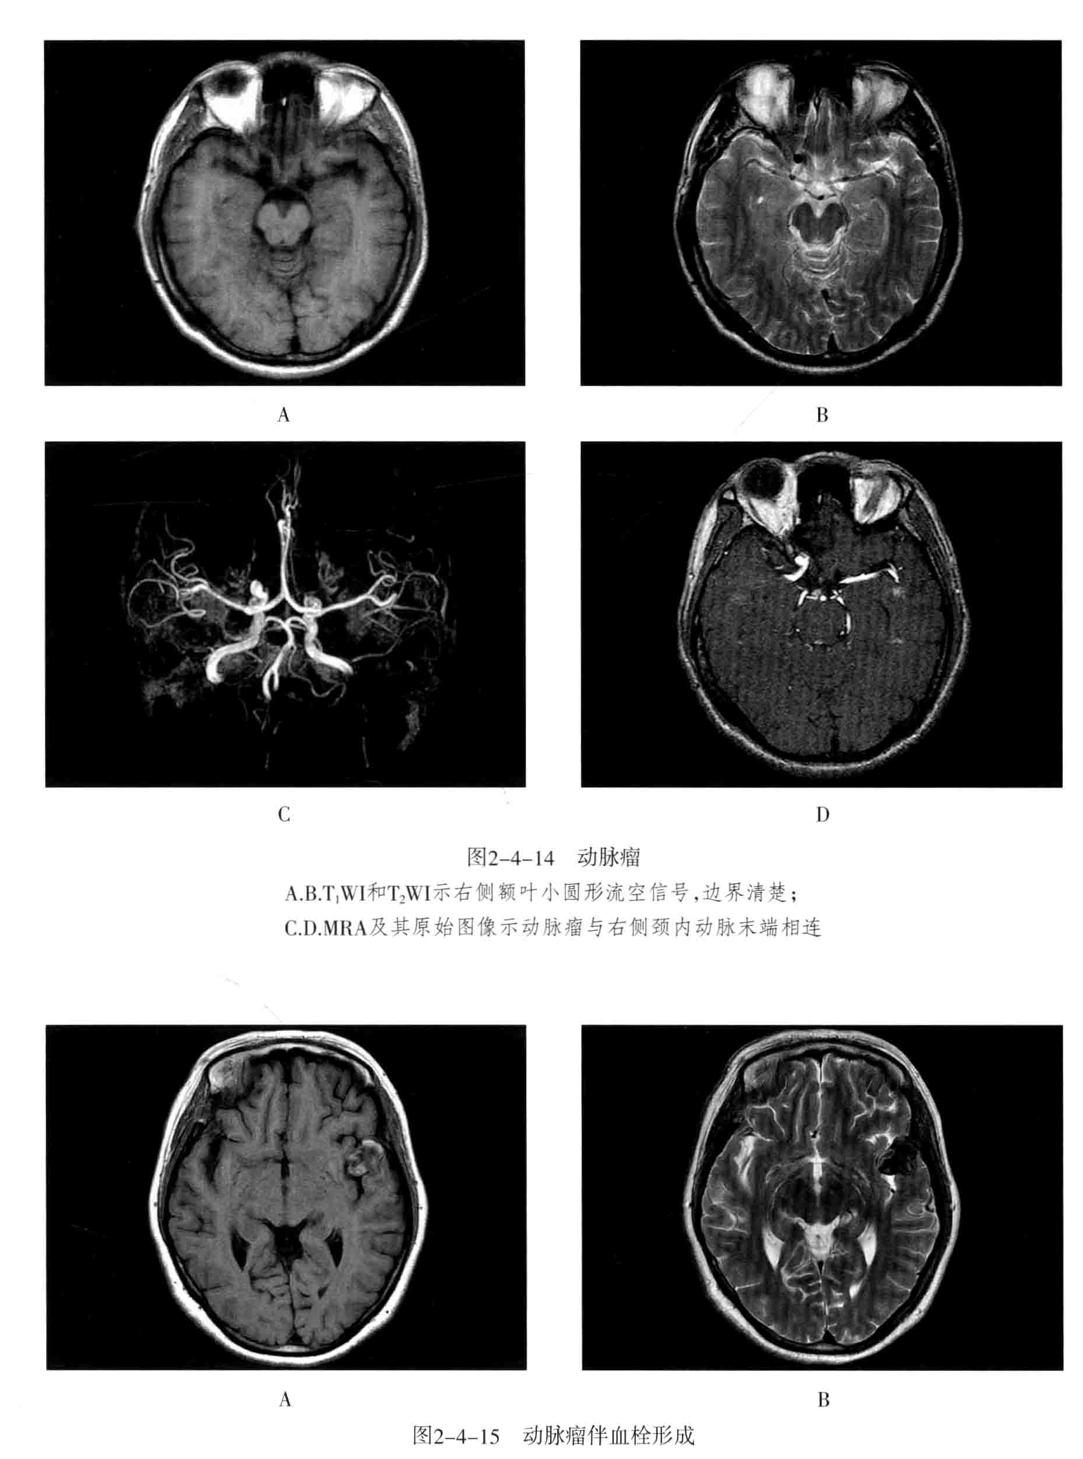

三、颅内动脉瘤

定义:颅内动脉局灶性异常扩大。

1. CT平扫为圆形高密度影,边缘清楚、增强有均匀强化,CTA或MRA可明确显示动脉瘤及其与载瘤动脉的关系。瘤样凸起。

2. 动脉瘤的瘤腔在T1WI、T2WI上均呈低信号,动脉瘤内有涡流时,也可产生轻微的不均质信号;瘤内血栓显示为高低相间的混杂信号。